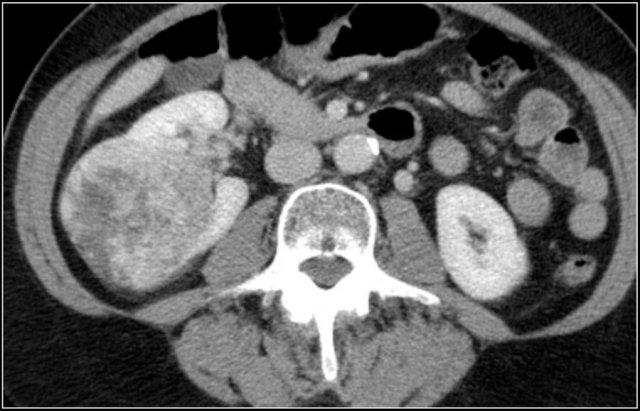

Đặc điểm điển hình của ung thư biểu mô tế bào sáng là ngấm thuốc mạnh trong thì vỏ-tủy (corticomedullary phase).

Điều này có thể khó đánh giá khi tổn thương nhỏ và nằm ở vỏ thận, vốn cũng ngấm thuốc mạnh.

Do đó, thì thận (nephrogenic phase) là thì nhạy cảm nhất để phát hiện các tổn thương này, vì nhu mô thận ngấm thuốc đồng nhất và đậm hơn so với khối u (hình minh họa).